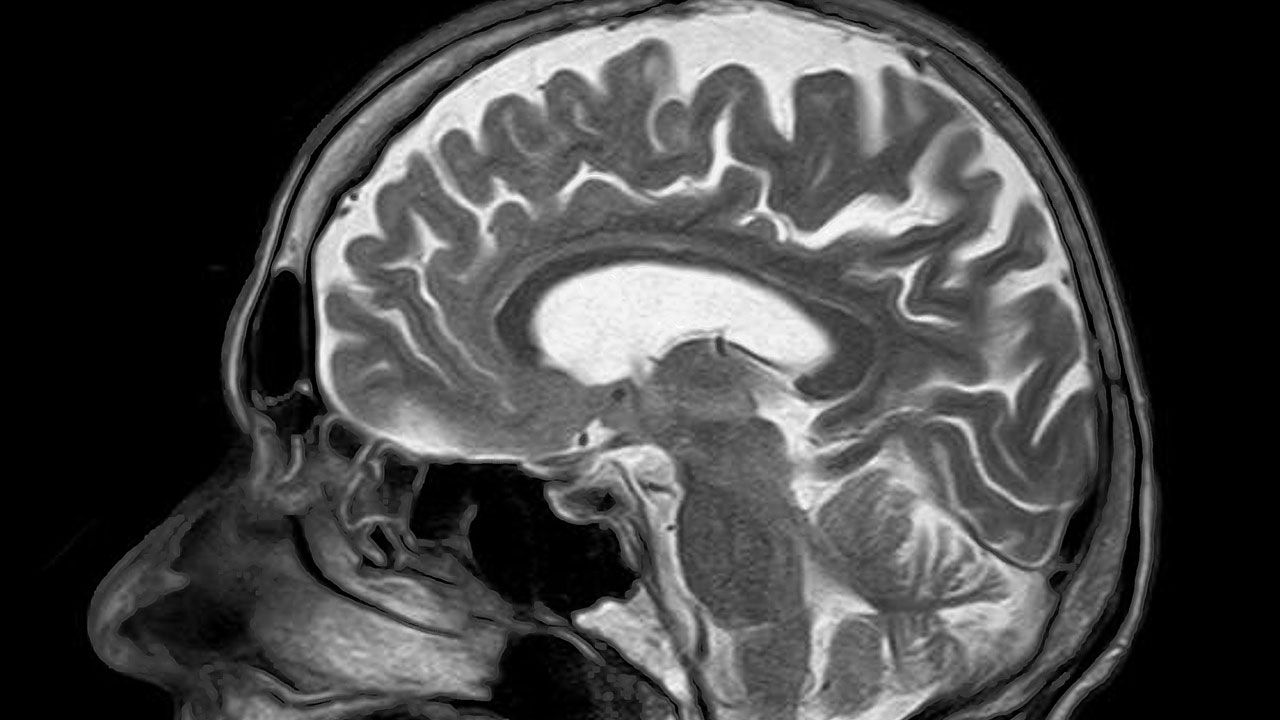

연구팀은 특히 비만 상태인 사람의 뇌에 쌓인 노화 세포가 불안증을 높이면서 신경정신학적 기능에 이상을 일으킨다는 점에 착안했다.

연구팀은 노화한 뇌세포 축적과 뇌 지질 침적 사이의 연관성을 알아보기 위해 나이 든 생쥐를 모델로 실험했다.

연구팀은 불안증을 통제하는 생쥐의 측두 뇌실(lateral ventricle)에 지질이 쌓이자 노화 세포도 급격히 늘어난다는 사실을 확인했다.